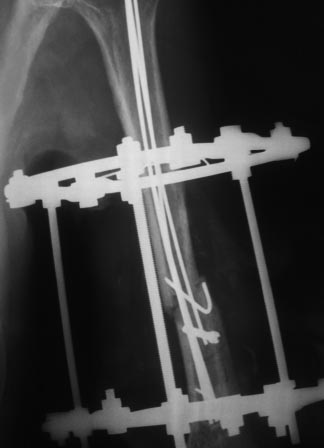

Уважаемые коллеги, прошу прощения за задержку ответа. Операцию проводили

27.11.13г по настоятельной просьбе докторов там, где был оперирован,

поэтому пришлось долго ждать контроль.Р-грамму и самого больного, только

сегодня приехали. Операция более 4 часов, во время операции установлено

полное повреждение лучевого нерва, концы булавовидно утолщены, дефект

2,5-см, с трудом и очень долго пришлось мобилизовать, частично был

замурован костной мозолью . Кость укорочена на 3 см, пластика типа

русского замка, в это время часть дистального отломка откололась,

поэтому пришлось фиксировать винтом, и еще косо спицей., и/м 4-мя

спицами, шов нерва, под нервом слой мышца, АВФ из двух колец с

компрессией. Р-снимки прилагаются.